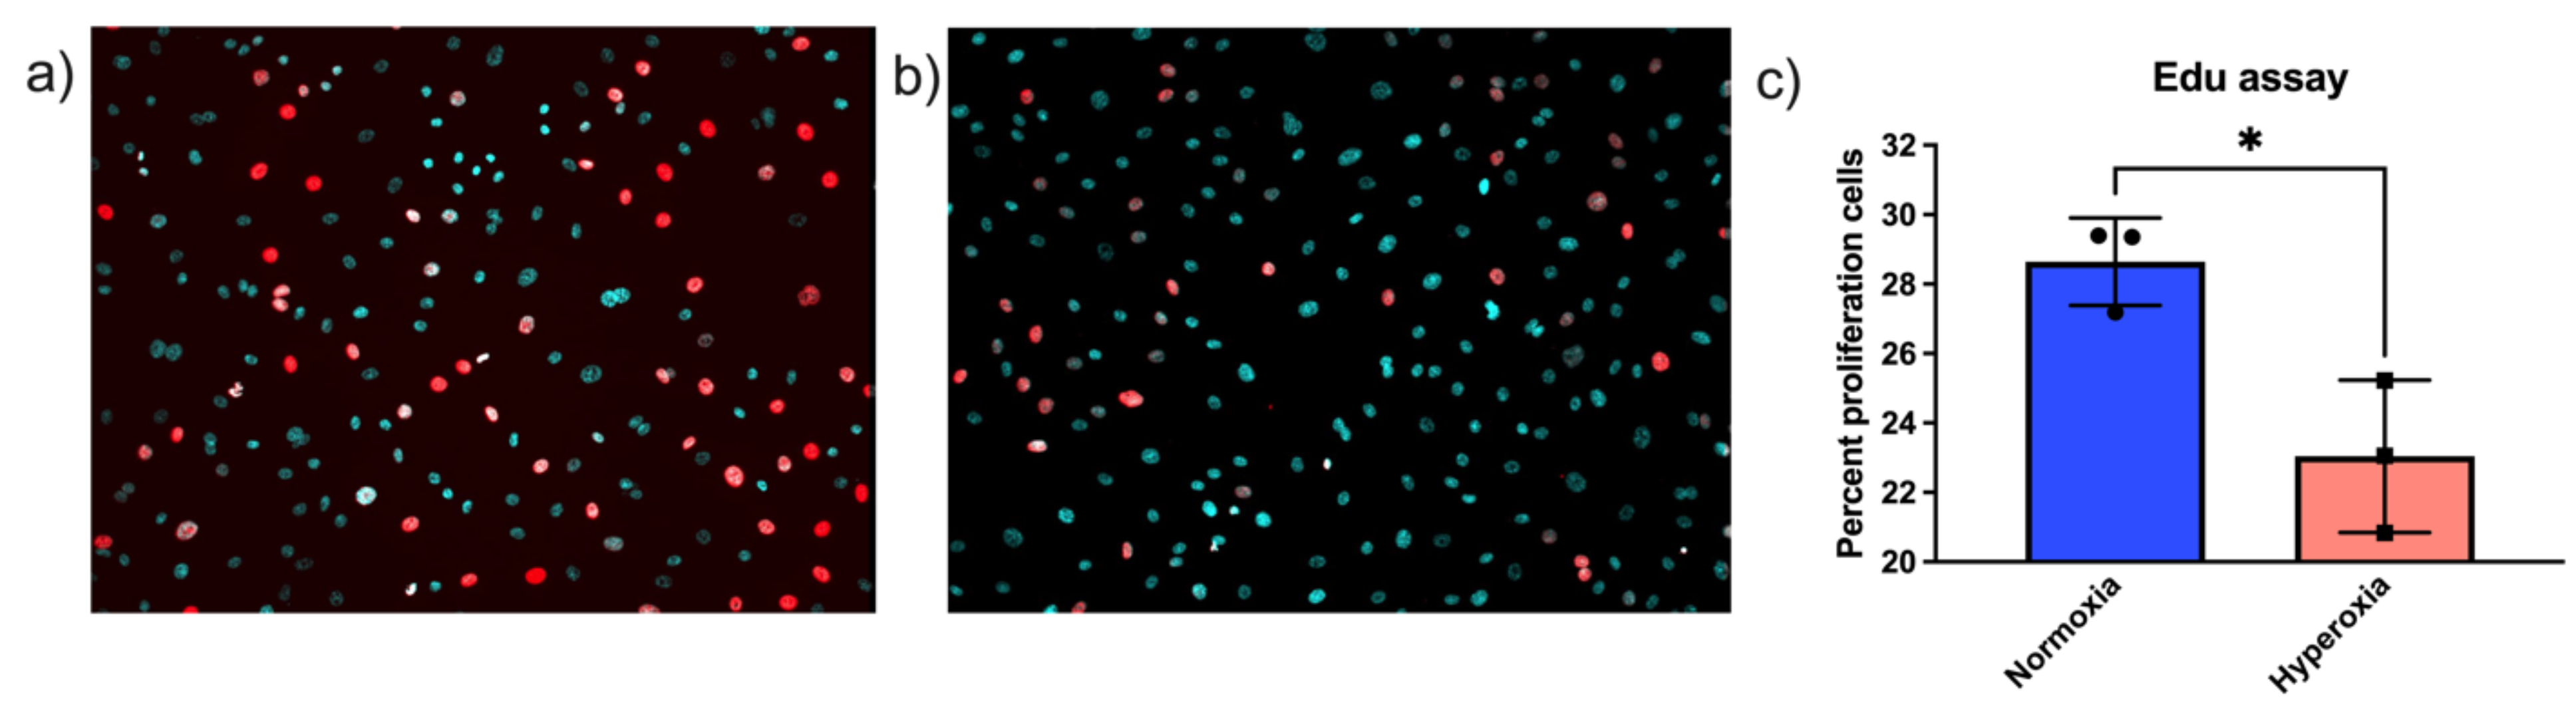

4.2. Edu and Hoechst Staining